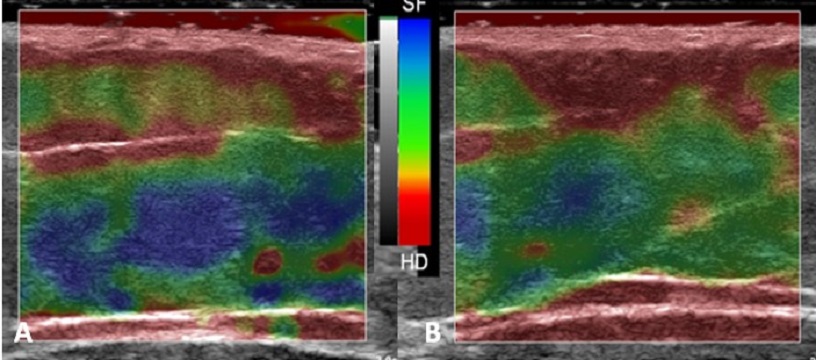

W ostatnim czasie coraz częściej wskazuje się również na użyteczność ultrasonograficznej elastografii w ocenie skuteczności prowadzonych terapii na ciało. Elastografia ultrasonograficzna jest zaawansowaną techniką obrazowania, która mierzy podatność tkanek na odkształcenie. W kontekście zabiegów na ciało dzięki możliwości precyzyjnego mierzenia zmian w elastyczności tkanek elastografia pozwala na monitorowanie postępów terapii, oceniając, czy w wyniku zabiegów doszło do zmiany twardości tkanki. Zgodnie z doniesieniami naukowymi, jeżeli twardość tkanki wzrasta, czyli jest ona mniej podatna na odkształcenia, dochodzi do poprawy wyglądu skóry, a także zaobserwowano, że dochodzi do zmniejszenia się cellulitu. Pomocniczo przy ocenie efektywności prowadzonych terapii obejmujących ciało można korzystać z takich parametrów jak pomiar grubości skóry właściwej, grubości naskórka. Parametrem, który – jak wynika z moich doświadczeń – może mieć dużą wartość diagnostyczną, jest ocena echogeniczności poszczególnych warstw skóry. Echogeniczność, czyli zdolność tkanki do odbijania fal ultradźwiękowych, powoduje, że część struktur na obrazach ultrasonograficznych jest ciemniejsza (hipoechogeniczna), a inne są jaśniejsze (hiperechogeniczne). Dzięki zmianom echogeniczności jesteśmy w stanie zobrazować np. stan zapalny czy zmiany ogniskowe. Obecnie badania dotyczące zmian echogeniczności w wyniku stosowania terapii na ciało są w początkowej fazie i z wyciąganiem wniosków należy jeszcze poczekać.